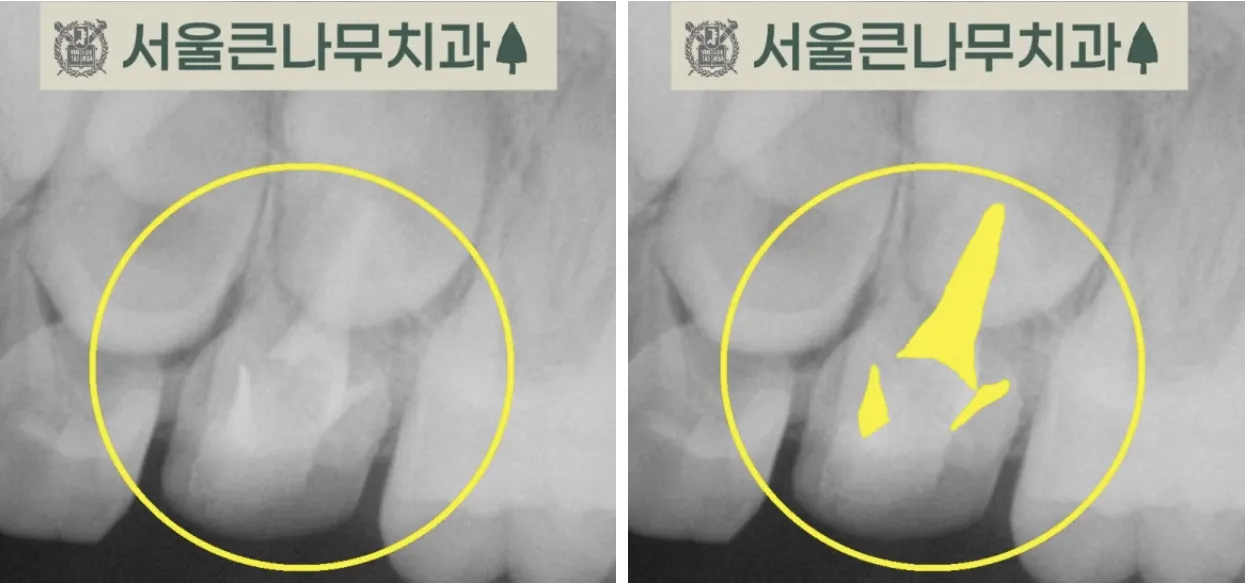

예를 들어보겠습니다. 사진에서와 같이 충치의 범위가 커서 신경을 침범했을 경우, 그로 인해 고름 주머니가 생겼을 경우 신경치료를 진행하게 됩니다.